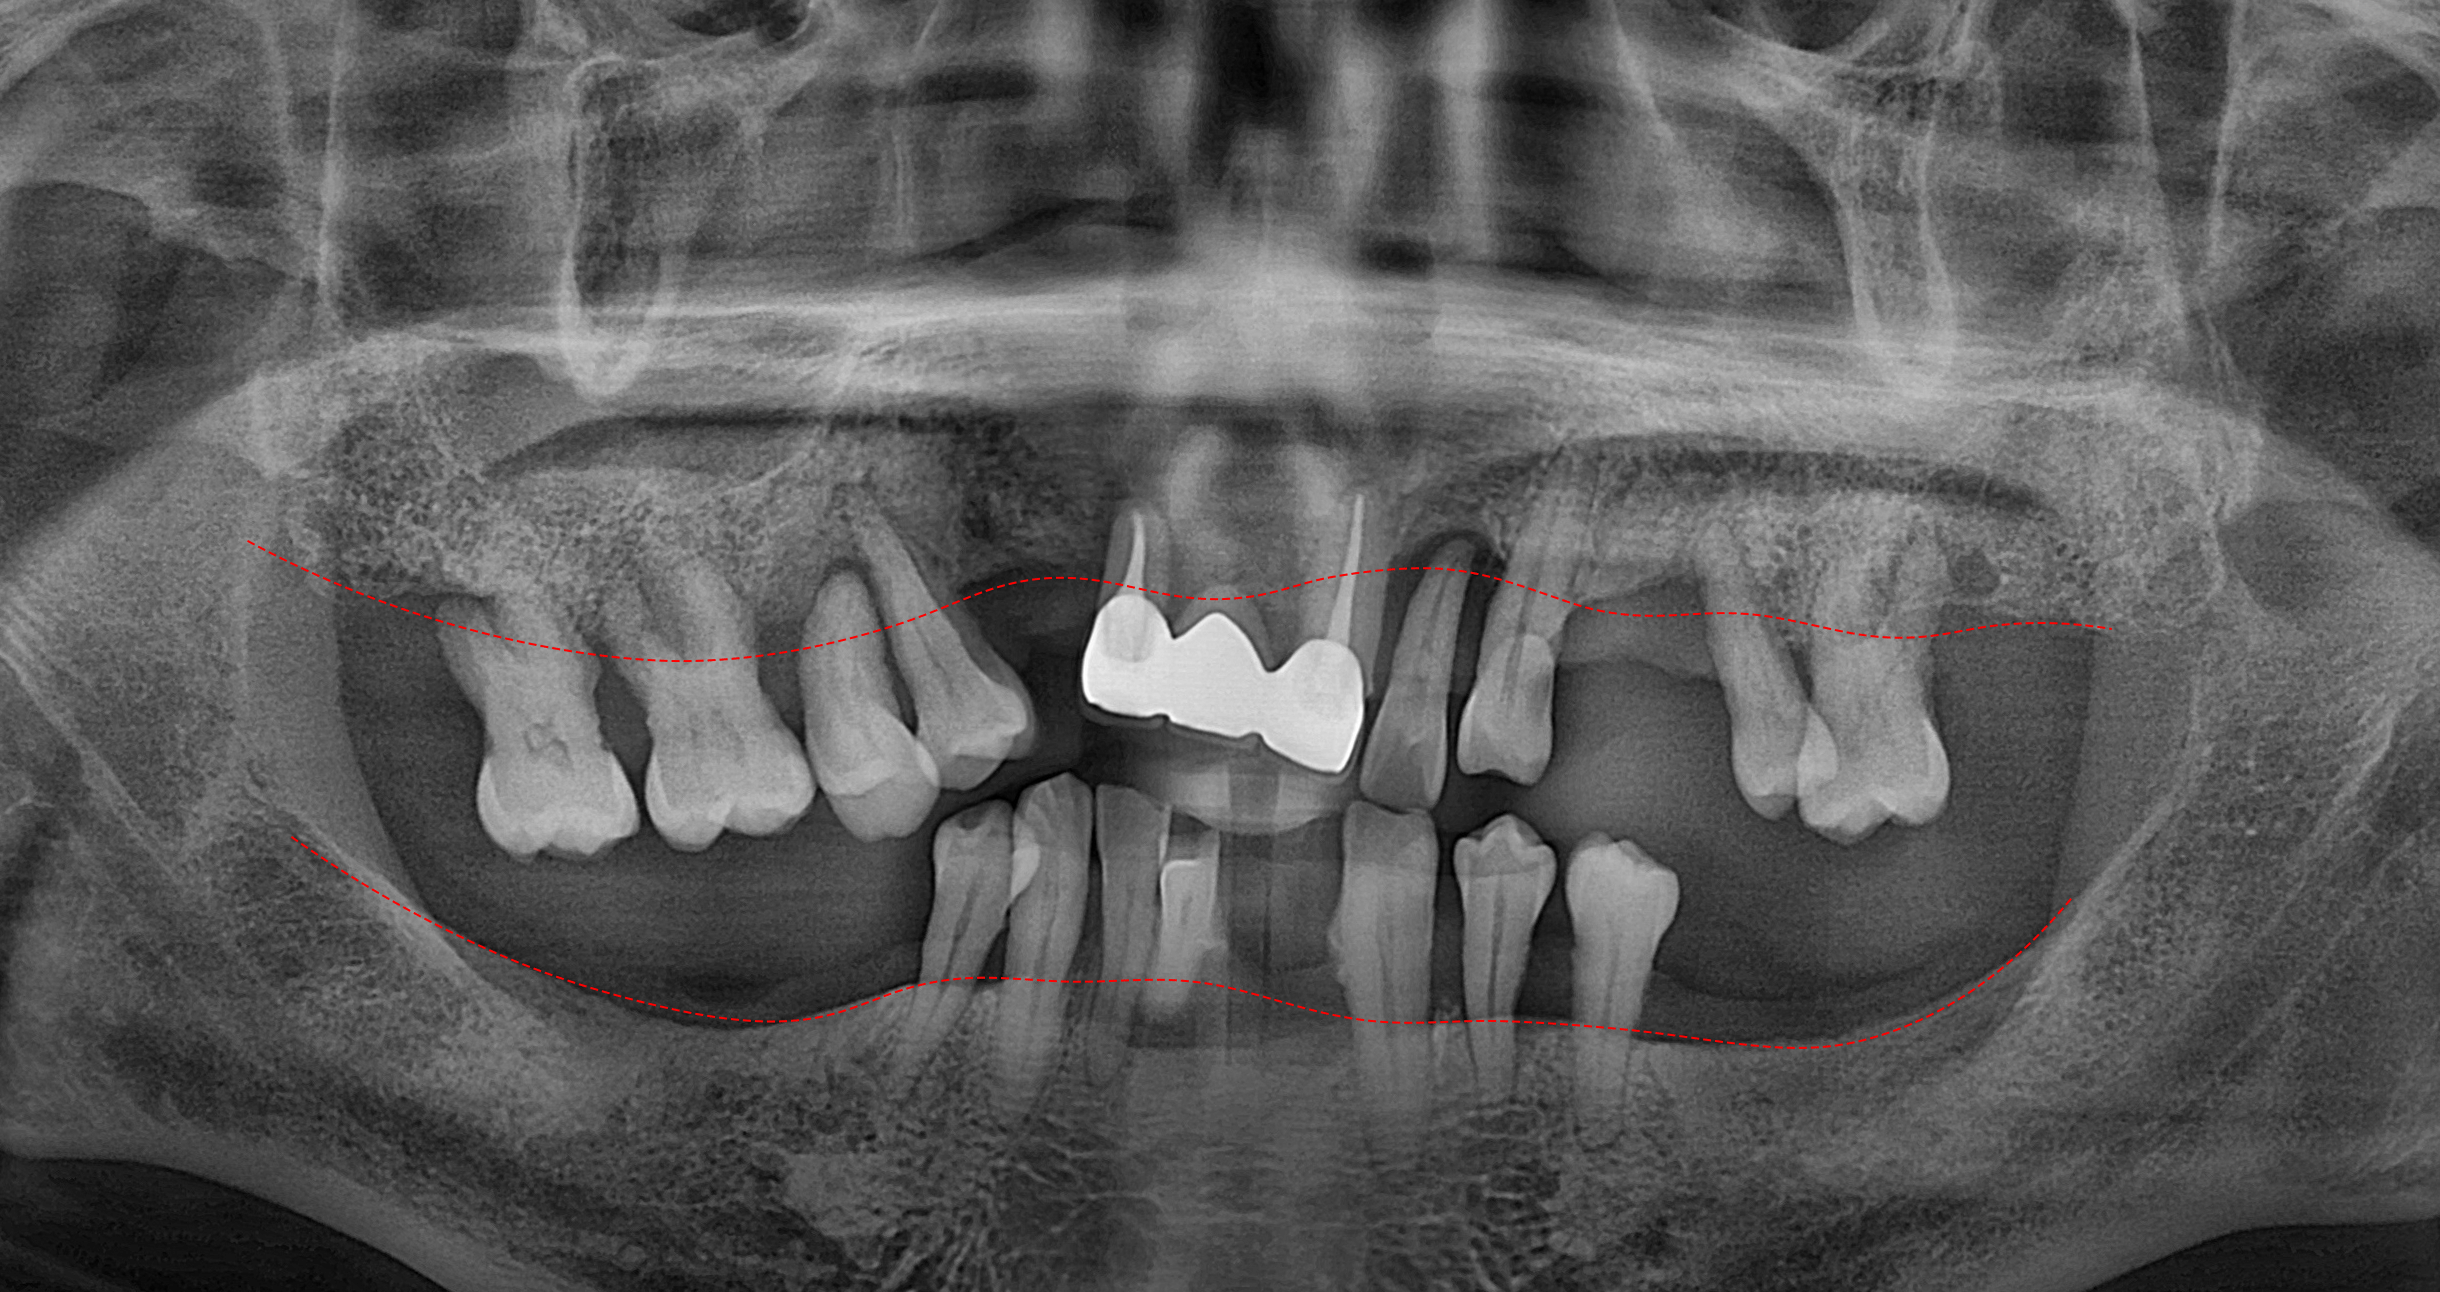

염증이 파급된 정도가 심하며

이로 인하여 잔존 치조골의 양이

매우 부족한 상태였습니다.

윗쪽에는 8개의 나사를 심고

아래쪽에는 10개의 픽스처를

식립하는 Plan 입니다.

이 과정에서 흡수된 치조골의 양이

너무 많아 골유도재생술(GBR)

즉 뼈이식을 함께 하기로 했습니다.

컴퓨터 분석 시뮬레이션을 바탕으로

식립이 알맞게 진행되었습니다.